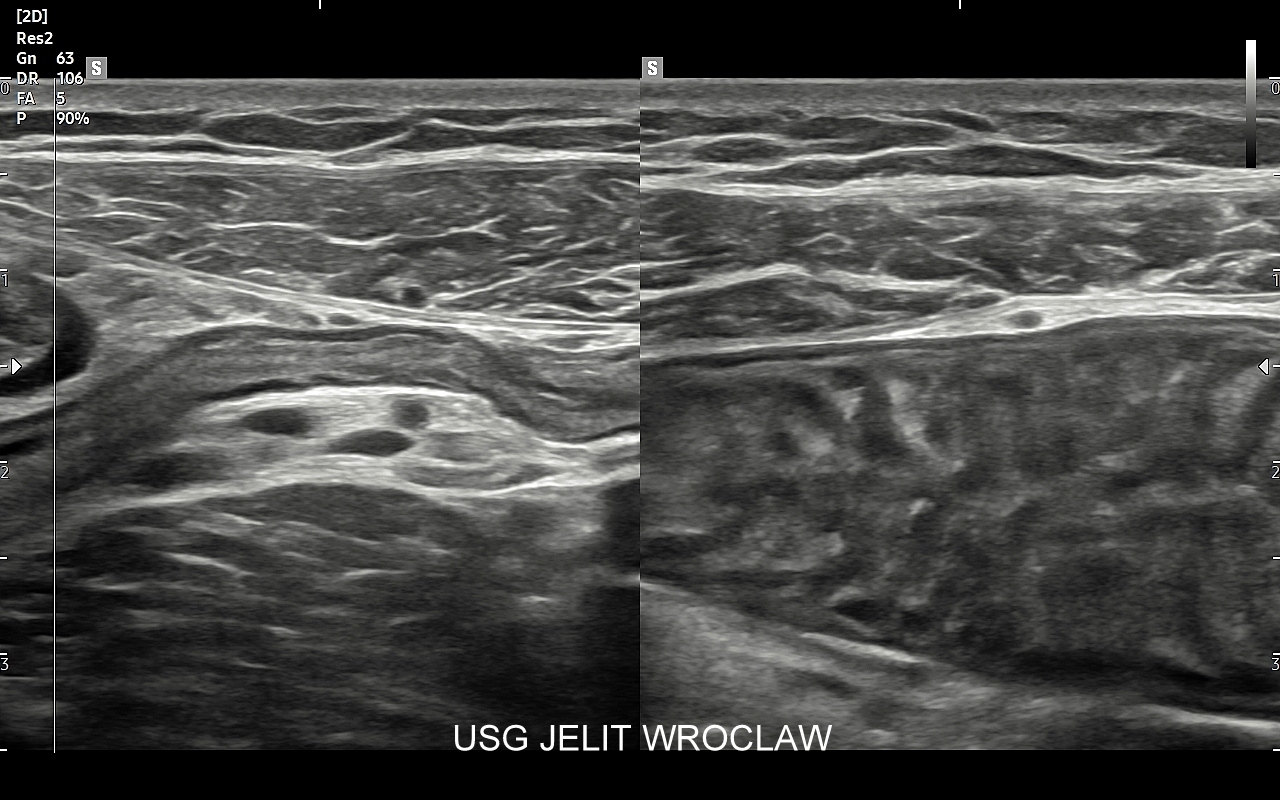

• badania USG wysokiej rozdzielczości,

Dr Tomasz Szczepański zajmuje się kompleksową opieką medyczną nad swoimi Pacjentami. W ramach Interdyscyplinarnej Pracowni USG Wrocław wykonuje szereg uzupełniających się badań, zarówno klasycznych, jak USG jamy brzusznej, USG tarczycy, USG piersi, pełen zakres diagnostyki USG Doppler, jak i wysokospecjalistycznych, w tym badania multiparametryczne (MPUS), badania USG z kontrastem (CEUS), ocena przetok dializacyjnych, badania USG Doppler przepływów nerkowych, czy badania USG twarzy